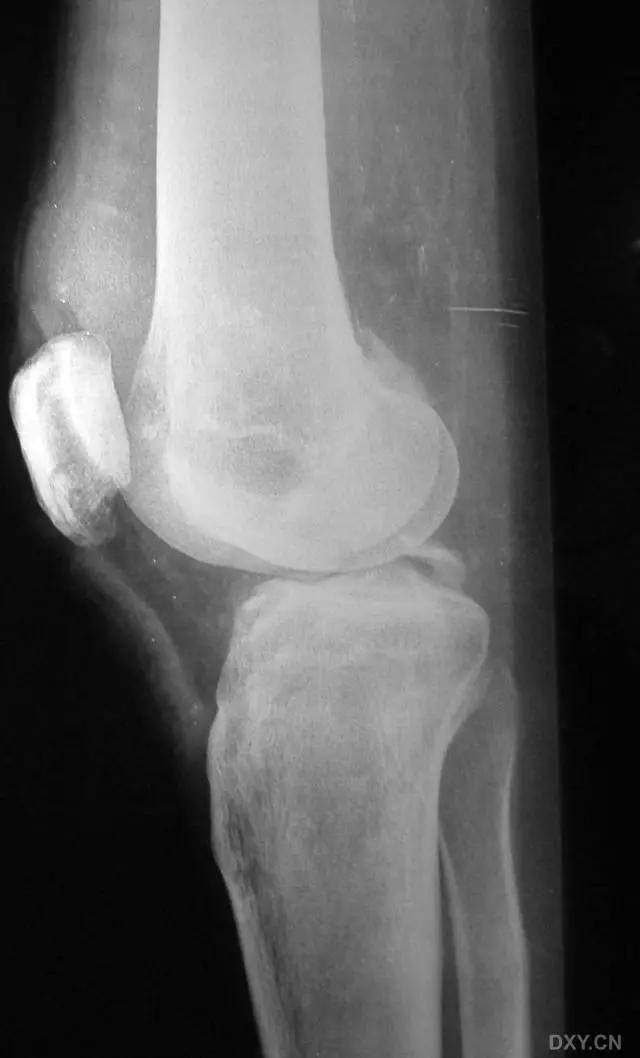

11. Bumper 骨折 (保险杆骨折)

是汽车保险杠撞击膝关节外侧,导致的胫骨平台粉碎性骨折,伴有软骨面挫裂和腓骨头骨折。初诊,X 线上正侧位很容易忽略平台的粉碎性,CT 平扫及重建可明确伤情,MRI 可了解副韧带及叉韧带情况。